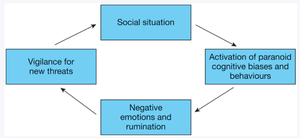

Paranoid Personality Disorder: Persistent distrust and suspicion of others, often interpreting their motives as malevolent.